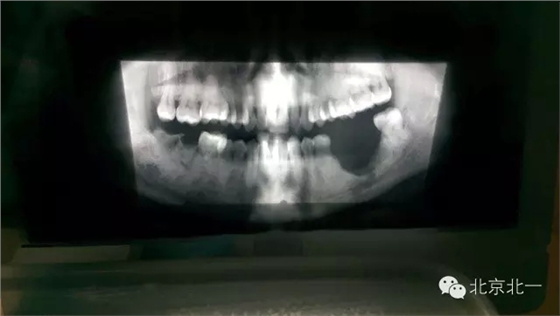

先看一例病例吧?拔牙前全景片。

圖二:拔牙后骨壞死,后被診斷為石骨癥,作為牙醫(yī)如果你還戰(zhàn)斗在拔牙一線,請(qǐng)正確認(rèn)識(shí)石骨癥。(這是《北一微創(chuàng)拔牙班內(nèi)部教材》局部章節(jié)節(jié)選病例分析)